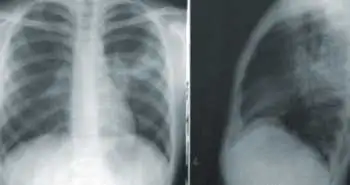

З лекції «Контроль болю при гострих респіраторних інфекціях».